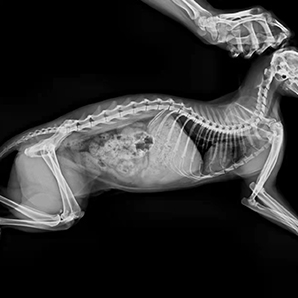

L'imagerie à faible dose est conviviale pour les animaux de compagnie tout en acquérant des images haute résolution pour le diagnostic.